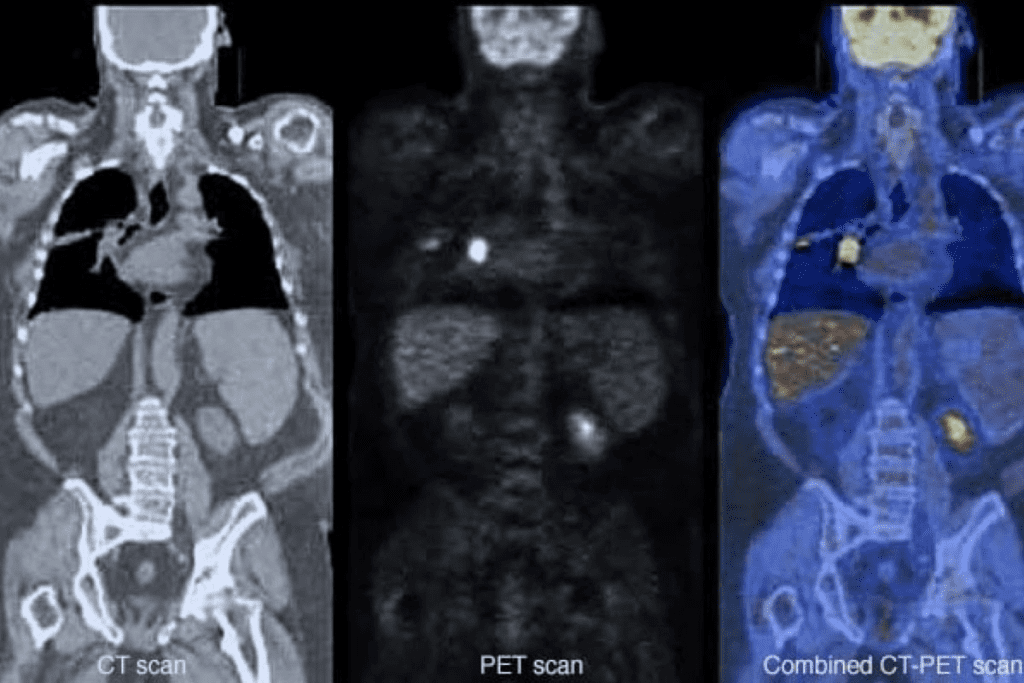

Positron Emission Tomography, or PET, scans are a crucial diagnostic tool in modern medicine, offering insights into the body’s metabolic activity. These scans help doctors diagnose and manage a variety of serious health conditions by providing detailed images of the body’s internal structures and functions.

A PET scan is a type of imaging test that uses a radioactive tracer to visualize the body’s metabolic processes. During the scan, a small amount of radioactive material is injected into the body, which is then absorbed by the cells. The PET scanner detects the radiation emitted by the tracer, creating detailed images of the body’s internal structures.

The information gathered from a PET scan can help doctors understand how well the body’s cells are functioning, identify areas of abnormal activity, and diagnose conditions such as cancer, neurological disorders, and cardiovascular disease.

How PET Scans Differ from Other Imaging Tests

PET scans differ from other imaging tests, such as CT scans and MRI scans, in that they provide information about the body’s metabolic activity, rather than just its structure. This makes PET scans particularly useful for diagnosing and managing conditions that affect the body’s metabolic processes.